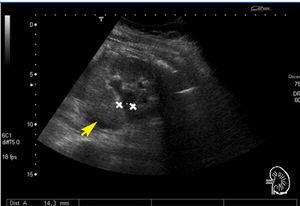

We treated a 28-year old pregnant woman (7 weeks gestation) that sought emergency treatment for intense weakness with vomiting and abdominal pain. She had a history of rhabdomyolysis secondary to severe hypokalaemia of an unknown cause, bilateral nephrocalcinosis, and nephrolithiasis (Figure 1). We reviewed the patient’s previous laboratory results and observed that she had hyperchloremic metabolic acidosis and hypokalaemia with persistently alkaline urine pH with several years’ evolution. Upon arrival in the emergency room, she had: AHT: 103/71mm Hg, HR: 78 systoles, deep abdominal palpation produced pain in the left hypochondria and fossa, with positive left renal percussion.

Figure 1. Simple abdominal x-ray